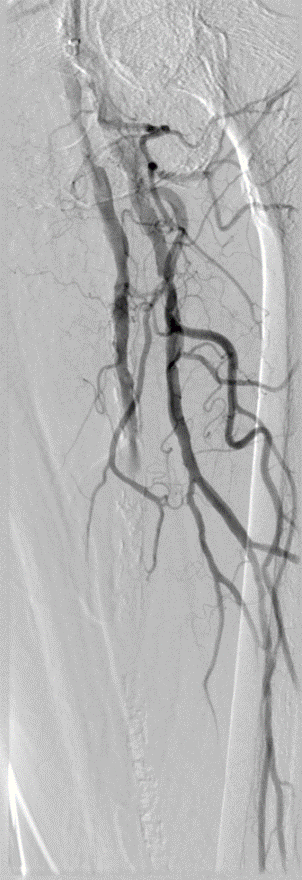

治疗策略演进:从单纯扩张到DEC理念

为应对内膜增生问题,业界尝试了多种方案:

药物涂层球囊(DCB):可抑制增生,但无法解决夹层和弹性回缩问题。

覆膜支架(如 Viabahn™, VB):通过物理隔绝,有效处理夹层和维持管腔,其长期通畅率优于单纯 DCB。

基于此,我们提出了“DEC”(Drug-Eluting Covered Stent)策略,即联合使用药物洗脱支架(DES, 如 Eluvia™)。该策略旨在:

利用 VB 的物理隔绝优势克服夹层与 recoil;

利用 DES 的药物缓释优势抑制两端及重叠区的内膜增生;

同时,DES 的裸支架平台对近端股深动脉等侧支影响更小。

开通:以内膜下技术为主,逆穿是常用且有效的辅助手段。

预扩:充分预扩张至关重要,需逐级使用高压球囊,最终达到 6mm 直径,以获得足够的管腔。

支架植入:遵循“由远及近”原则,先放置远端 DES,再覆盖中段 VB,最后处理近端。利用 Eluvia 的可调节性优化重叠。

后扩:常规使用 6mm 高压球囊进行后扩张,确保支架充分贴壁和管腔获得。

用药:术中术后必须充分抗凝,推荐“双通道”抗栓方案(如利伐沙班+阿司匹林),以模拟 bypass 的血流动力学效果。